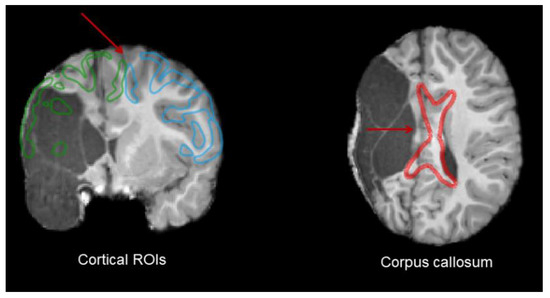

2.4. Lesion Characterization

3.2.2. Corpus Callosum